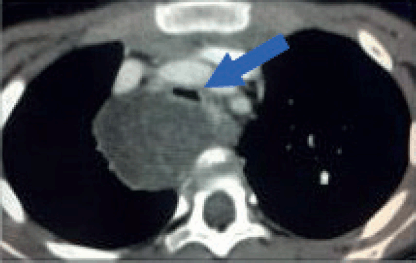

Airway compression and cardiopulmonary function must be assessed preoperatively. Patients with clinical or radiological evidence of airway compression require pulmonary function tests (VEF1). Both pulmonary and cardiac function play a separate role in anaesthetic risk. For patients with airway compression and risk of ventilatory collapse during induction anaesthesia, it is critical to maintain spontaneous ventilation and avoid the use of muscle relaxants until the airway is secured (Figure 5). Flexible bronchoscopy may be a useful adjunct for difficult airway management or to confirm airway patency. On the other end of the spectrum, patients at high risk of cardiovascular collapse may require extracorporeal membrane oxygenation to tolerate the procedure.

Figure 5. Tracheal compression. Contrast-enhanced axial CT image of a 6-year-old girl with a large tumour at the upper right posterior mediastinum. The lesion crosses the midline over the anterior surface of the vertebral body, at the level of the manubrium. Both, arterial and venous mediastinal great vessels are selectively enhanced with contrast. The trachea is severely compressed by the tumour (Blue arrow). This patient is at high risk of ventilatory collapse during the induction of anaesthesia.